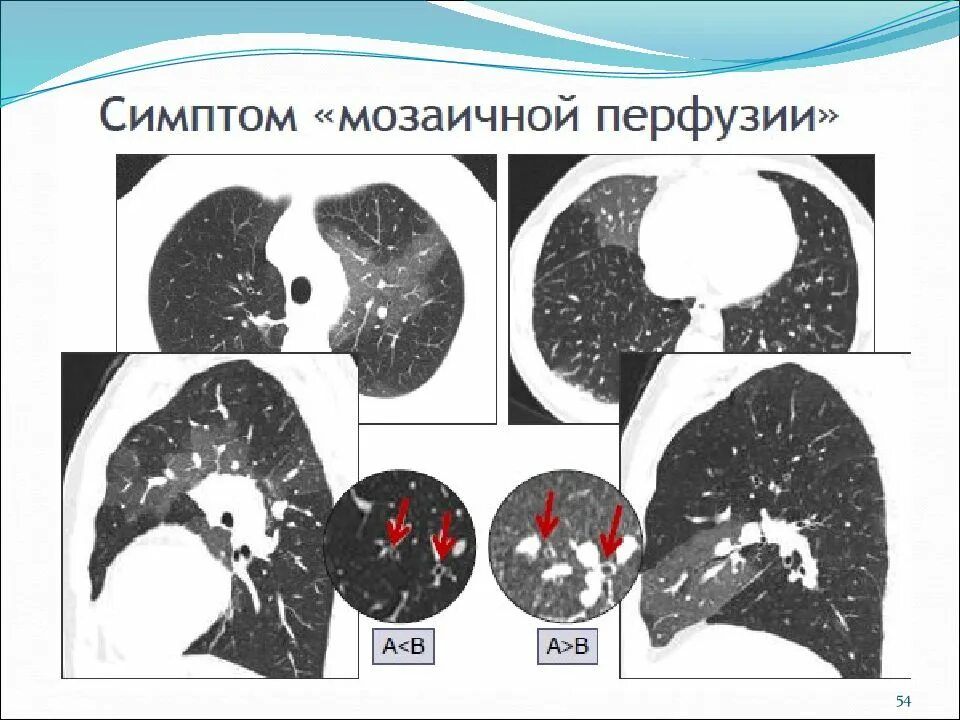

Мозаичная перфузия